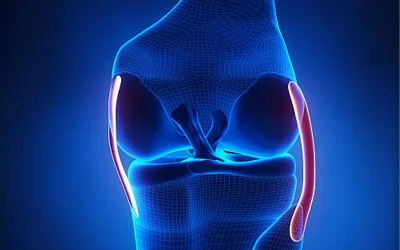

از علت تا درمان آرتروز زانو شامل چه مواردی میشود؟ به طور کلی میتوان گفت که امروزه آرتروز زانو یکی از بیماری های شایع در بین عموم مردم به شمار میرود و در چند سال اخیر افراد بسیاری دچار این بیمار...